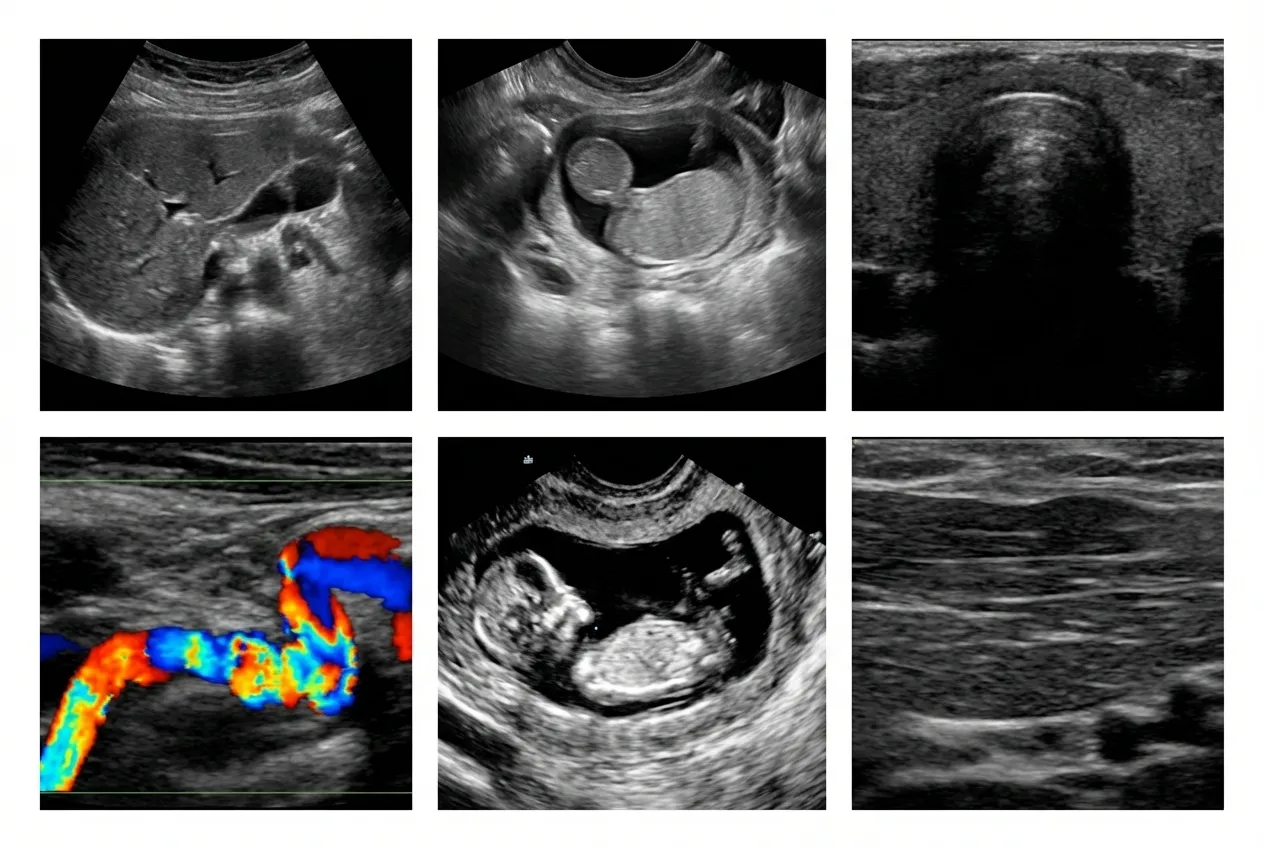

Abdominal Ultrasound

This ultrasound scan evaluates organs such as the liver, kidneys, and gallbladder, helping detect pain causes, infections, and digestive conditions with accurate and reliable imaging results.

Pelvic Ultrasound

Pelvic ultrasound imaging helps assess reproductive organs, bladder conditions, and internal concerns, supporting accurate diagnosis and treatment planning with clear imaging results.

Vascular Ultrasound

Vascular ultrasound evaluates blood flow in arteries and veins, helping detect blockages, clots, and circulation issues with precise, non-invasive diagnostic imaging technology.

Pregnancy Ultrasound

Pregnancy ultrasound provides detailed imaging to monitor fetal development, confirm pregnancy stages, and ensure both mother and baby are progressing safely throughout each stage.

Soft Tissue Ultrasound

This ultrasound scan evaluates muscles, tendons, and soft tissues to detect injuries, swelling, or abnormalities, helping guide accurate diagnosis and effective treatment.